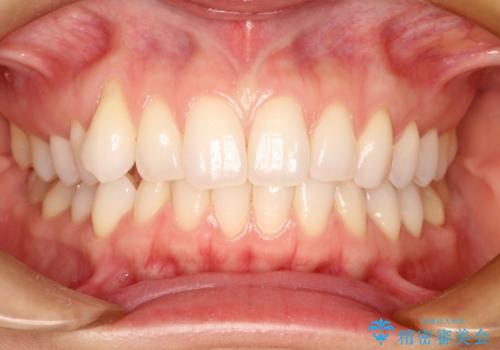

八重歯をマウスピース矯正で治療し、レーザーホワイトニングを行った症例

- 主訴:「右上犬歯を引っ込めて、歯並びをキレイにしたい」

右上の八重歯を気にされてご来院されました。結婚式を控えていたため挙式にまでに可能な限りキレイにしたいとのことでした。

また、ホワイトニングも一緒にご希望されたため、挙式のタイミングに合わせてレーザーホワイトニングを施術させていただきました。

右上の犬歯の歯茎は矯正前から退縮を起こしていましたが、矯正後もその退縮に関しては変化がありませんでした。今回は患者様が歯肉退縮に関しては治療をご希望ではありませんでしたが、当院ではこのように歯茎が下がり露出した根面を、歯茎を移植することでカバーし見た目を改善する手術を行っています。